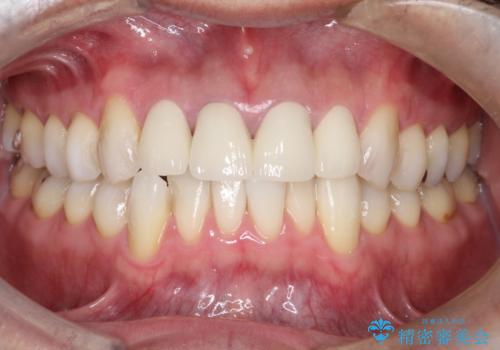

審美的な改善はもちろんのこと、ぴったりとしたものを装着することで、歯茎の発赤も改善されました。